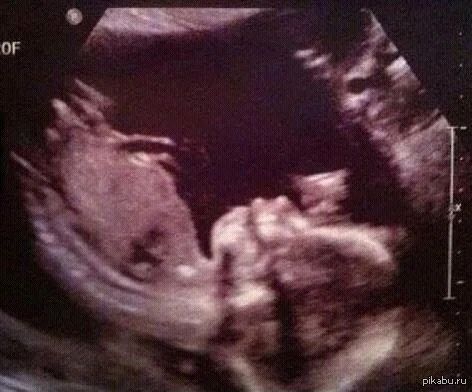

Снимок узи, помогите «расшифровать»

Hobn R, Мы знаем, что мальчик 😄 Вопрос в том, что на снимке) Где ноги, где гениталии. Но уже поняли 👌🏽

Да, это ножки и машонка)

Это вот внизу горизонтально левая согнутая нога, вверху - часть правой согнутой ноги, а посередине яички и пенис. Взгляд снизу, так сказать)